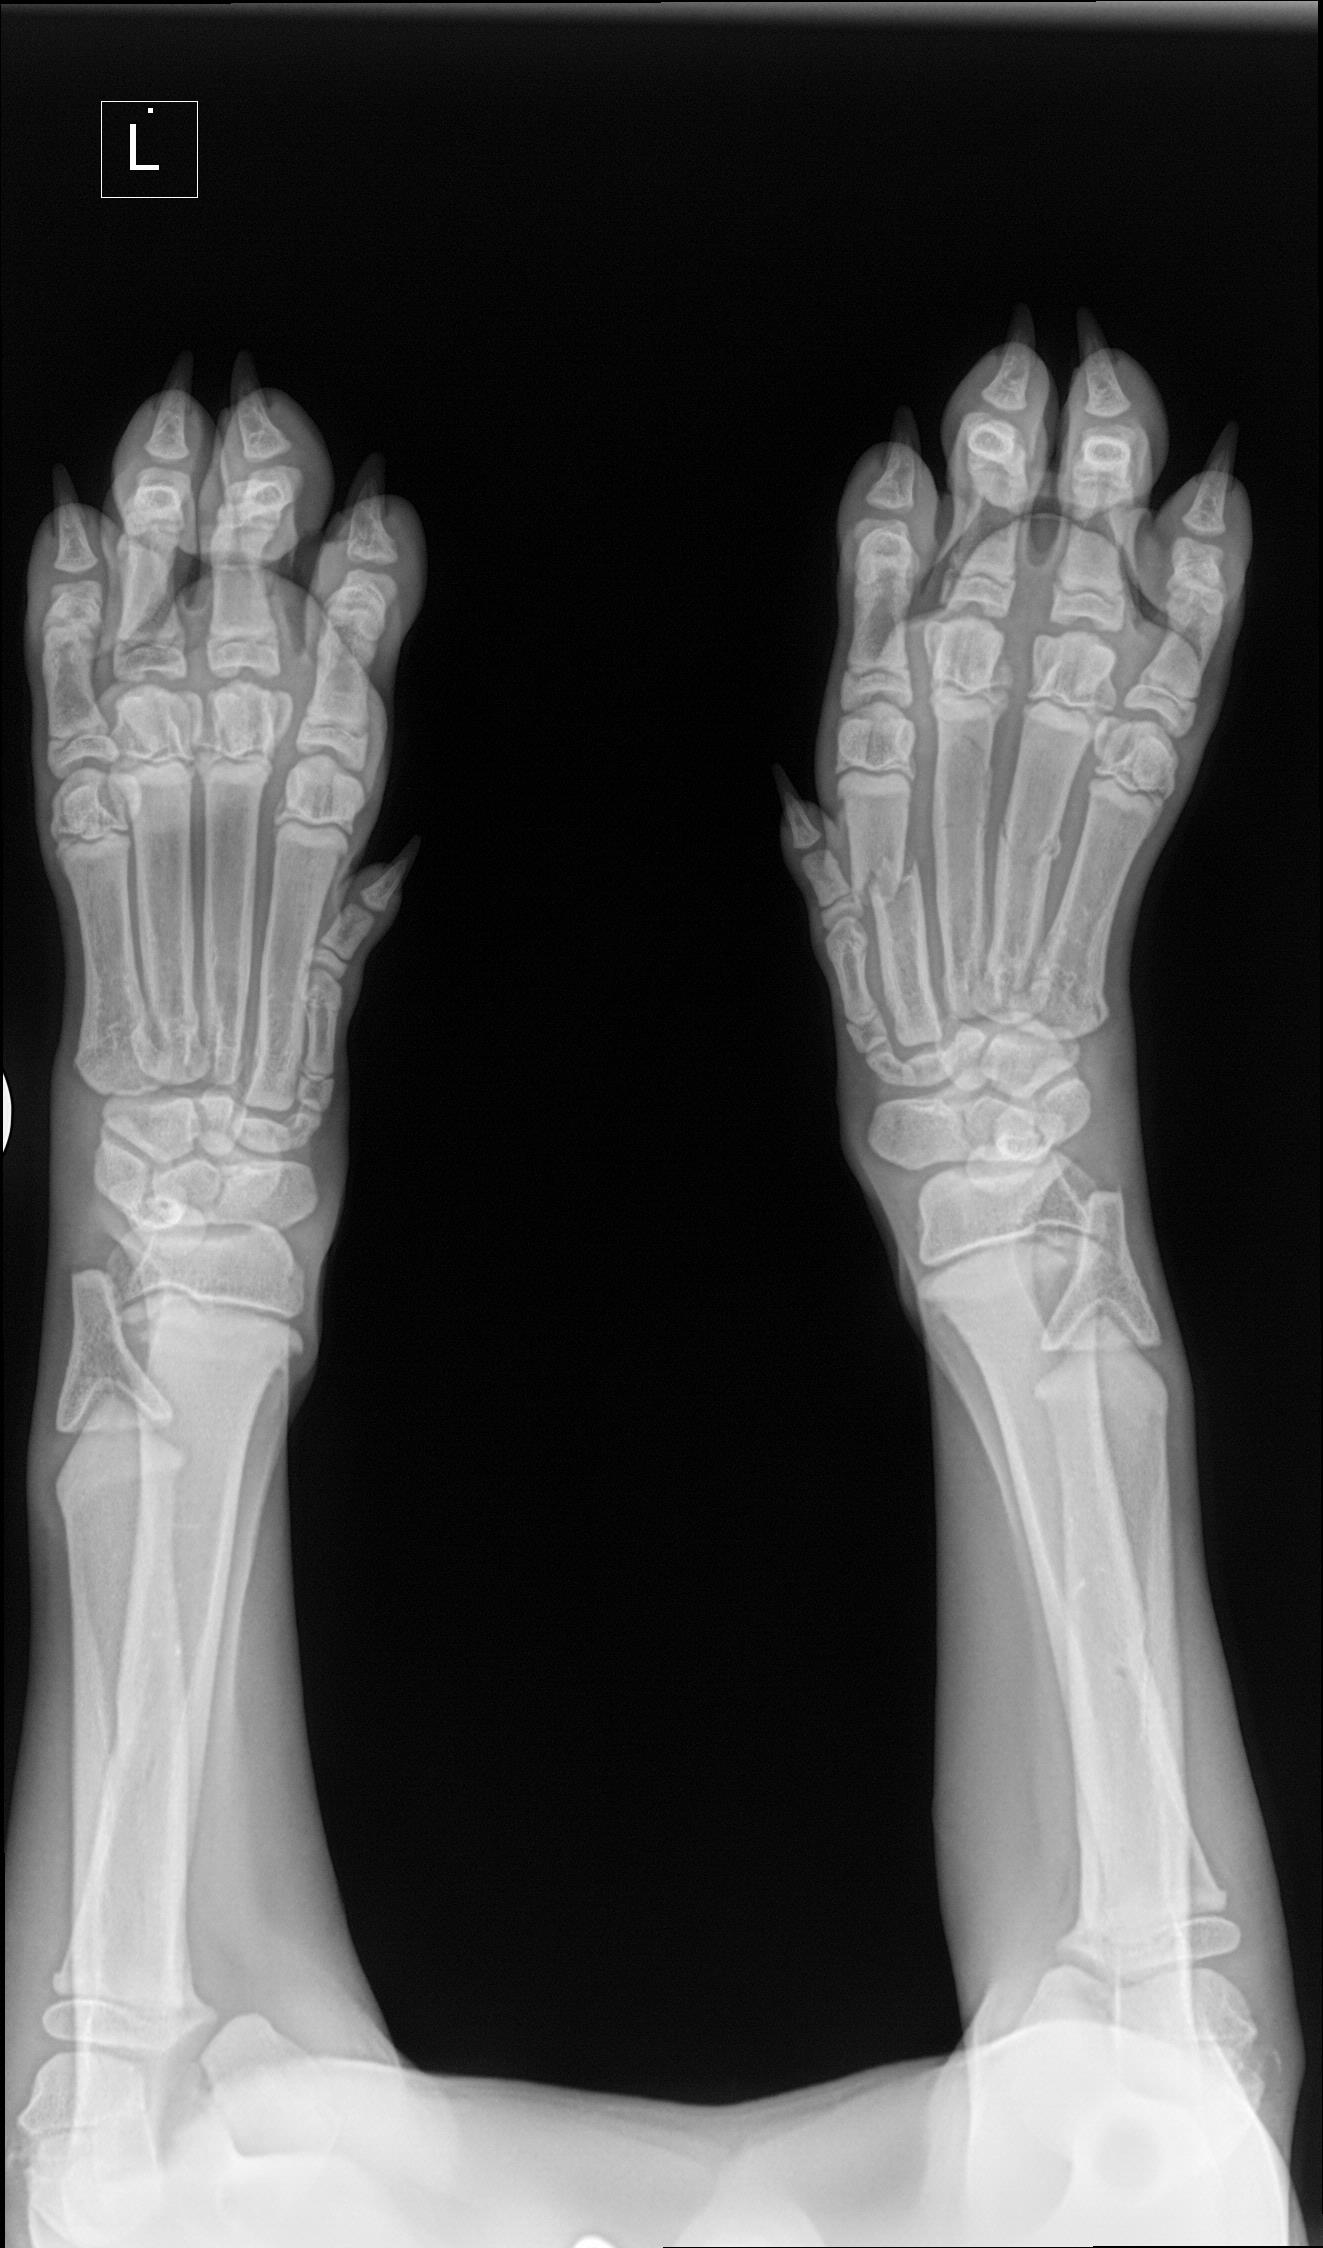

OREO (Am. Bulldog)

Sweet Oreo had a Bear of a Procedure.  She was in Surgery for four hours with Dr. Chris Gauthier at CVRC.  Surgery was a lot more complicated than we realized it was going to be.  We knew the injury was older, but it had already formed a massive amount of scar tissue which made surgery tough.

The Surgeons are always looking at me when I describe what I see as possible as if I have one eye in the middle of my forehead. My idea of opening her leg up and looking around and then closing back if things don't look hopeful never quite work out.   There are layers on top of layers that have to be debrided before you can even see the broken bone.  Once you have done all of that, you need to go ahead and surgically repair the area as best you can and then get out.  They take the correct extended version, and in my mind, I see a quick in and out which is not possible.   This was the only was to give Oreo any chance of getting mobility back in that joint.

This adorable little puppy has stolen everyone's heart.  Oreo has remained in ICU because of swelling and a slight fever but is doing much better today.  Oreo's Medical Team did range of motion exercises to keep her joint as flexible as possible.  She is still pretty stiff from the swelling, but they did manage to get a little bit of movement.  We will continue with her rehab when she arrives back at our Rehab Facility.

We have to keep her as pain-free as possible without numbing her leg, so she injures it for us to do her exercises.  Those exercises are critical in her long-term recovery.   The leg that is cast is healing beautifully, and she is using it all the time.    Oreo has a couple of months of Rehab before we can say, we have given her back all the movement she will ever have in that leg.  Once that is complete, we will determine if she is better with the leg or if we need to remove it.